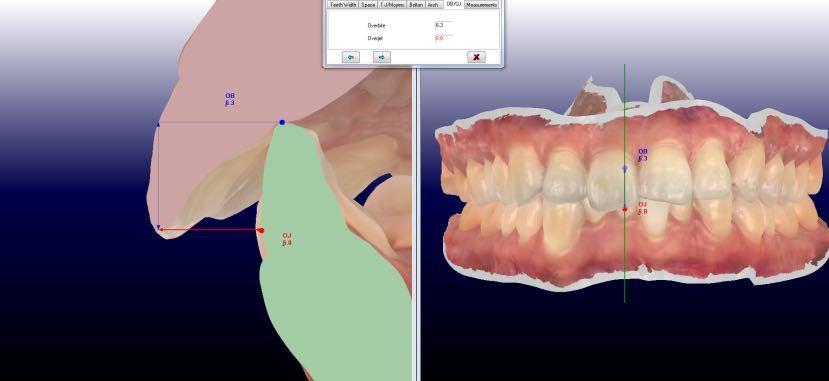

覆盖5mm,覆合3mmspee曲线深约1mm,前牙bolton比:78%,全牙bolton比:92%

上牙弓拥挤2mm;下牙弓拥挤0.5mm 2.spee曲线深度:左侧1mm;右侧2mm 3.